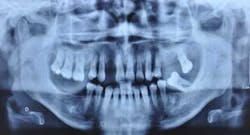

Fig. 1: Panoramic X-rays of a 40-year-old woman

A 40-year-old woman, with no medical history except that she is a smoker (five cigarettes a day), is visiting us for an oral rehabilitation. Her chief complaints are teeth mobility and an esthetic concern since her maxillary front teeth are moving forward. The patient also suffers from dental anxiety.